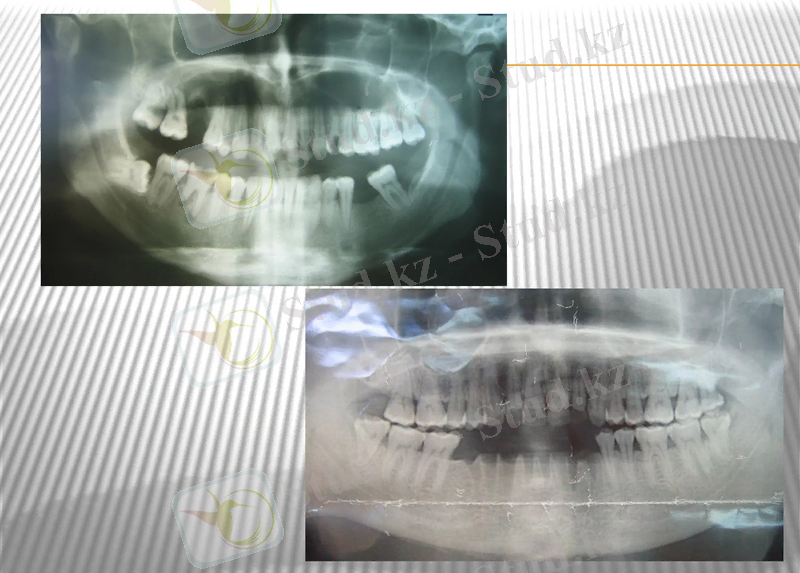

Остеомиелит- жақ сүйектері кемігінің қабынуы. Көбінесе өршімелі іріңді перицементиттен туындап, астыңғы жақ сүйегінде үлкен азутістердің тұсында дамиды. Остеомелит жедел және созылмалы ағымды . әдетте іріңдіпреиодонтитпен сырқаттанып, организмі бактериялық стрептокок, жасыл іріңді таяқша, коли-таяқша сияқты антигенмен байқалады. Алдымен альвеоларлық өскіннің кемікті кеңістігі іріңдейді кейін жақ сүйек денесіне жайылады. Ол жерде сүйек табақшалары лакуналы не тегіс сипатта ыдырап жұқарады.

Микроциркуляциялық арнаның тамырларында тромбылар түзіліп саңылауы бітеліп, сүйектің кей жерлері өлескеге айналады, бөлініп сүйектік секвестр қалыптасады. Секвестр іріңмен қошалып секвестрлік қуыста орналасады. Үдеріс ұзаққа созылса пиогенді мембрана пайда болады. Мембрана ішіне лейкоциттер толады. Грануляциялық тінінің сыртқы қабатында талшықты дәнекер тін өсіп қабыққа айналып секвестрлік қуысты сүйектен шектейді. Кейде іріңнің әсерінен секвестрлік қабықпен сүйек жіне оның қабығы дажидеп жыланкөз қалыптасып секвестрлік қуыс ауыз қуысыпен жалғасады, бет терісі арқылы сыртқа шығады. Секвестр сыртқа шығарылған соң жаңа сүйек табақшалары пайда болады.